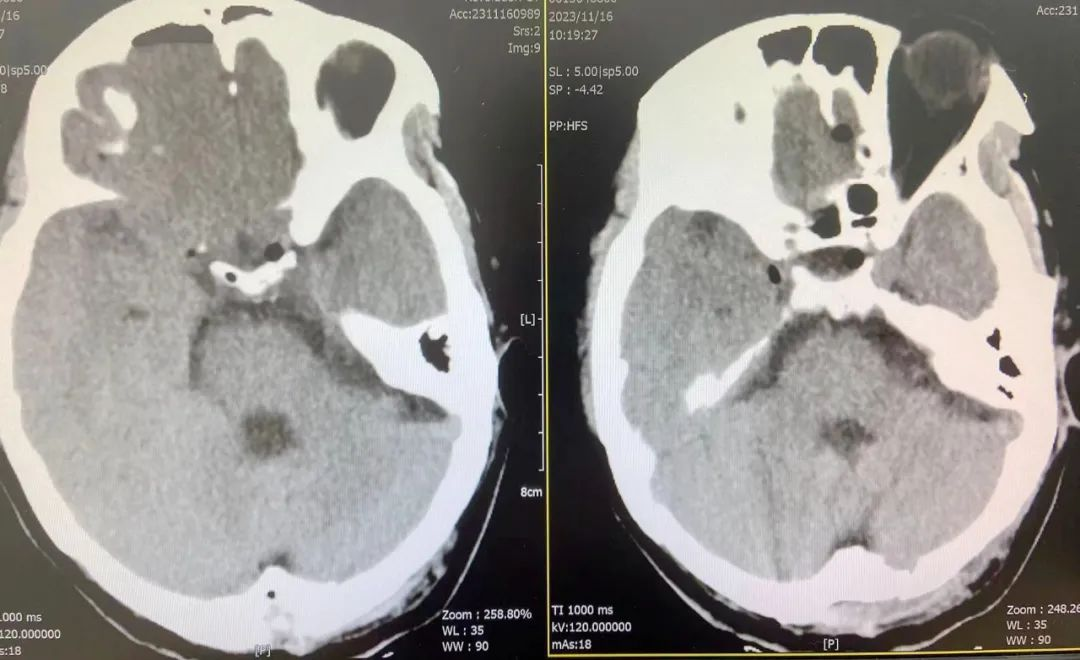

▲术后复查CT提示:血管瘤完整切除

术后患者视物晃动、头痛症状明显缓解,术后恢复快,第二天即可下床活动,语言流利清晰,无吞咽困难,饮水呛咳等,无后遗症。得知成功摘除这个不定时炸弹,又没有后遗症,患者及家属都非常高兴。